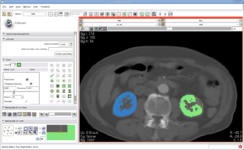

Interactive Editor: This new module allows interactive segmentation with robust 2D and 3D algorithms

EM Segmenter: A configurable image segmentation tool that uses intensity distributions along with atlas information